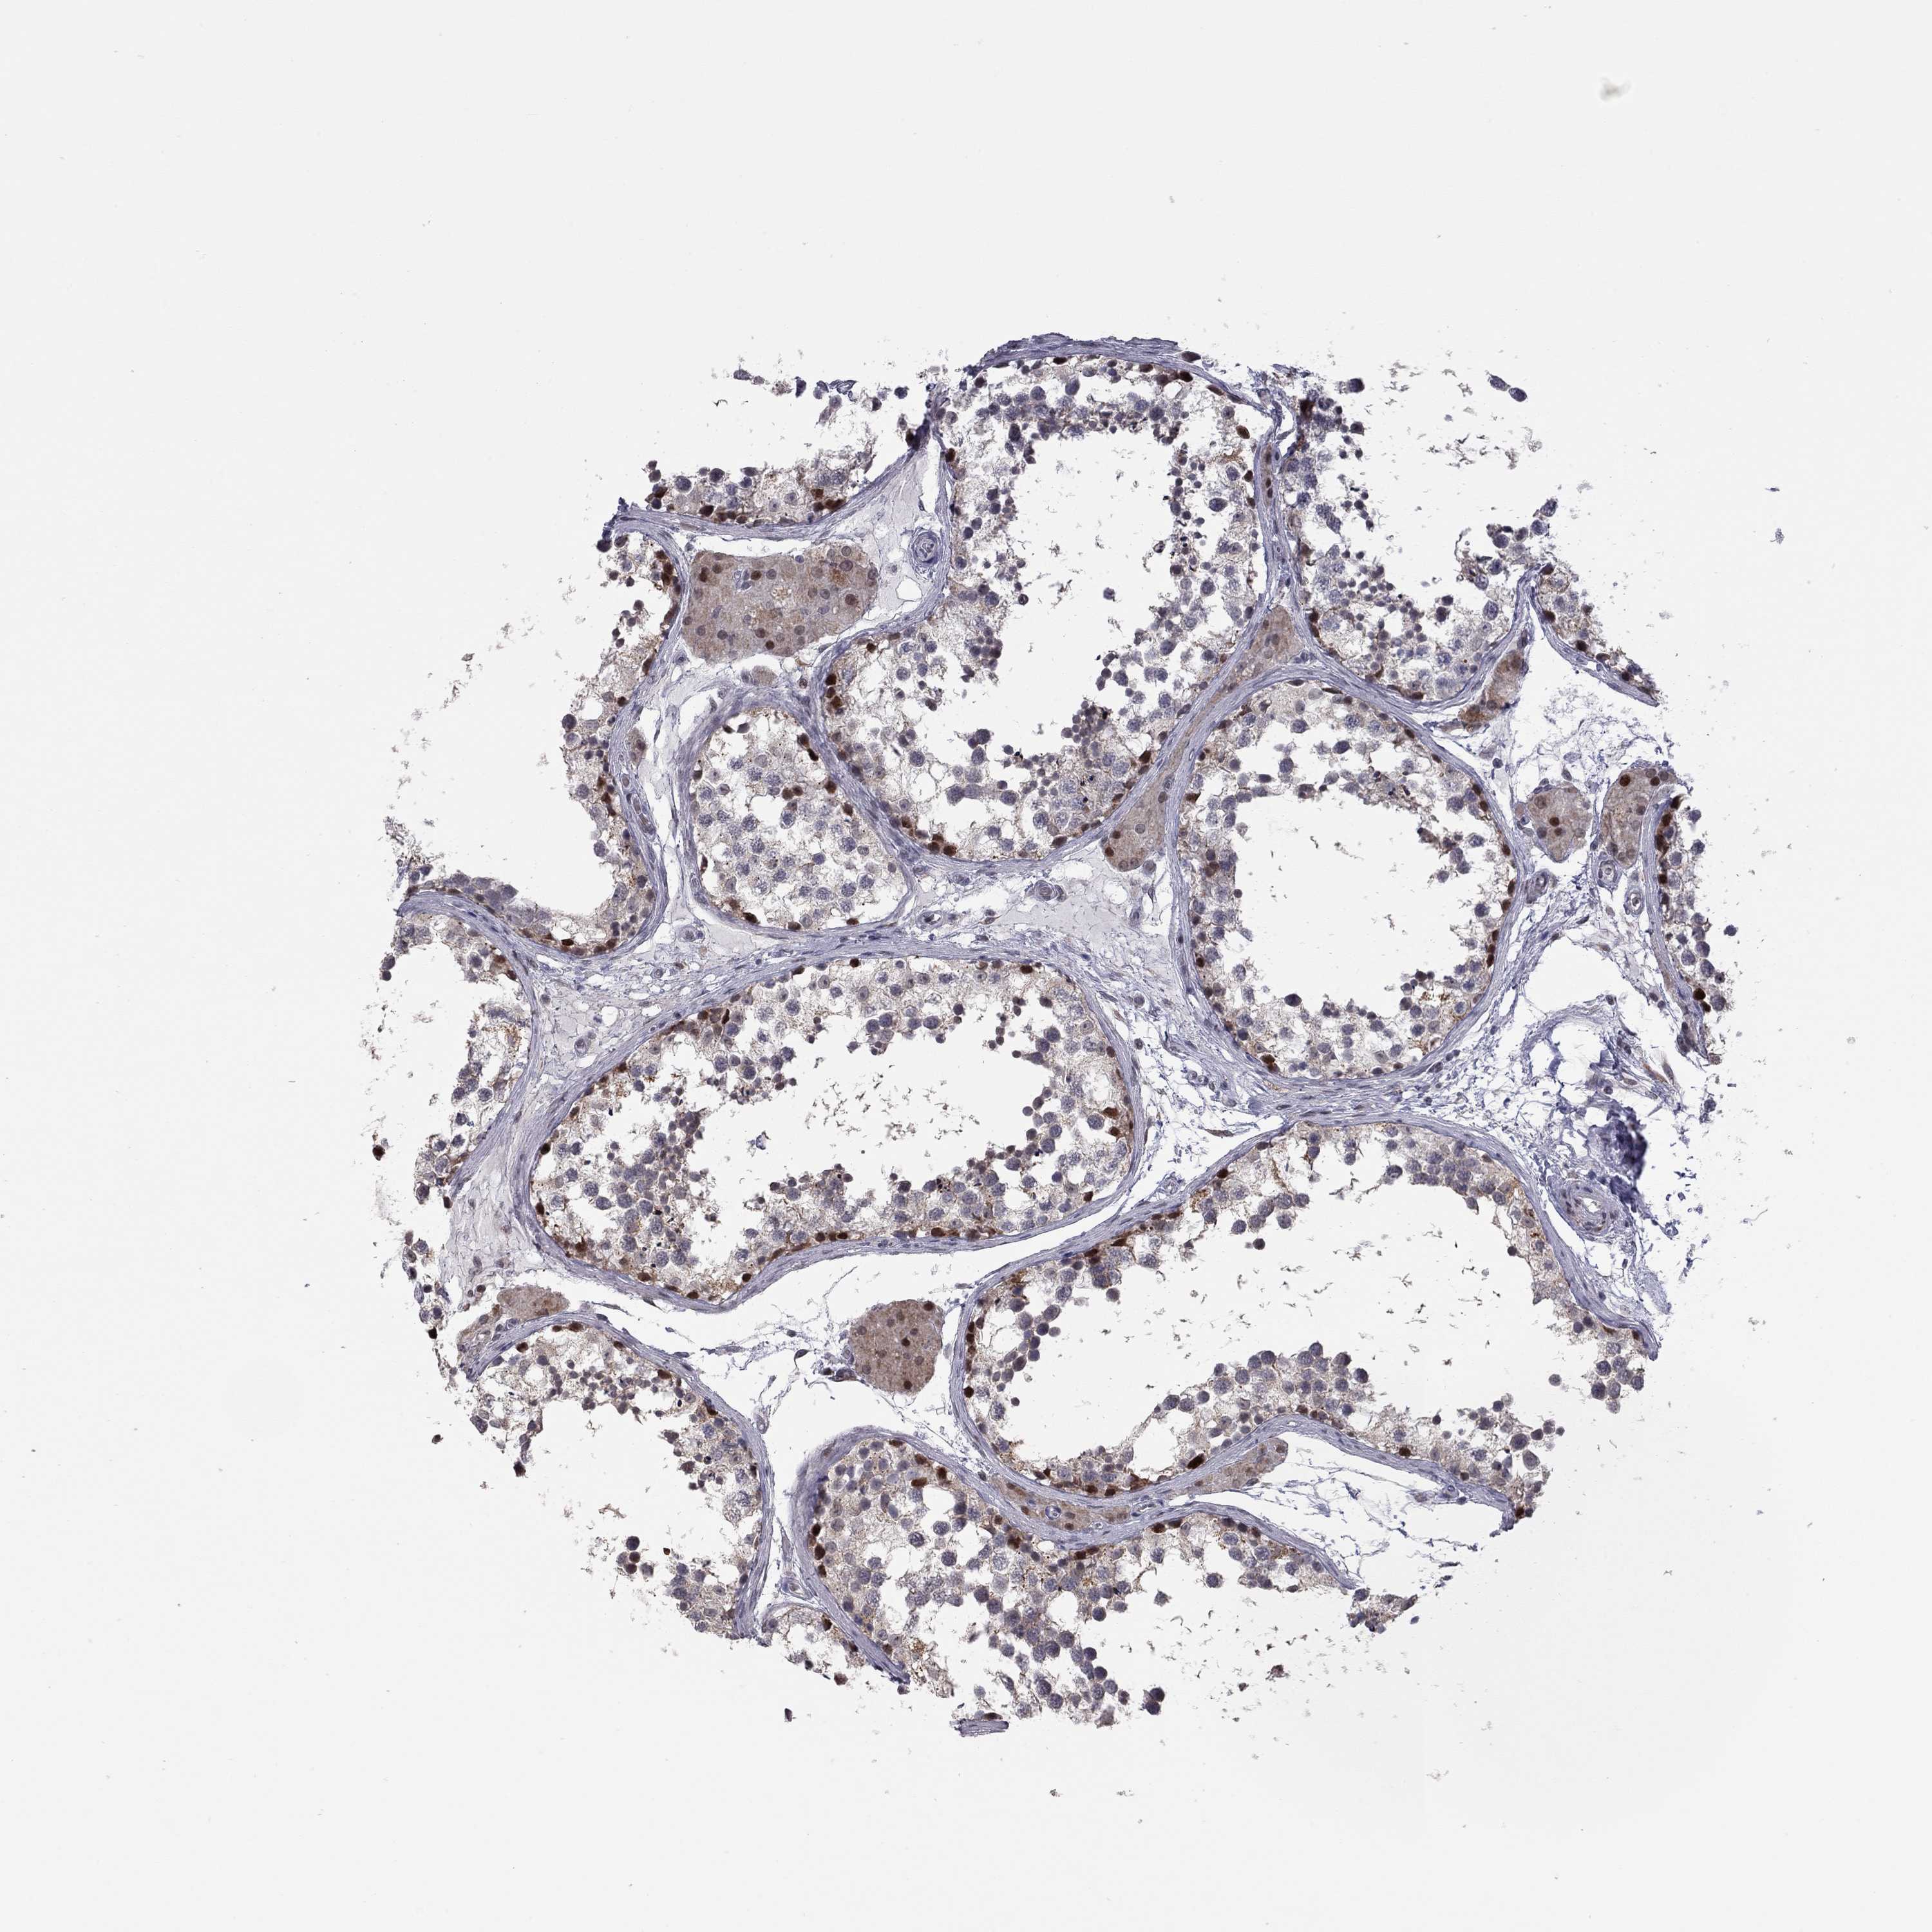

MC3R